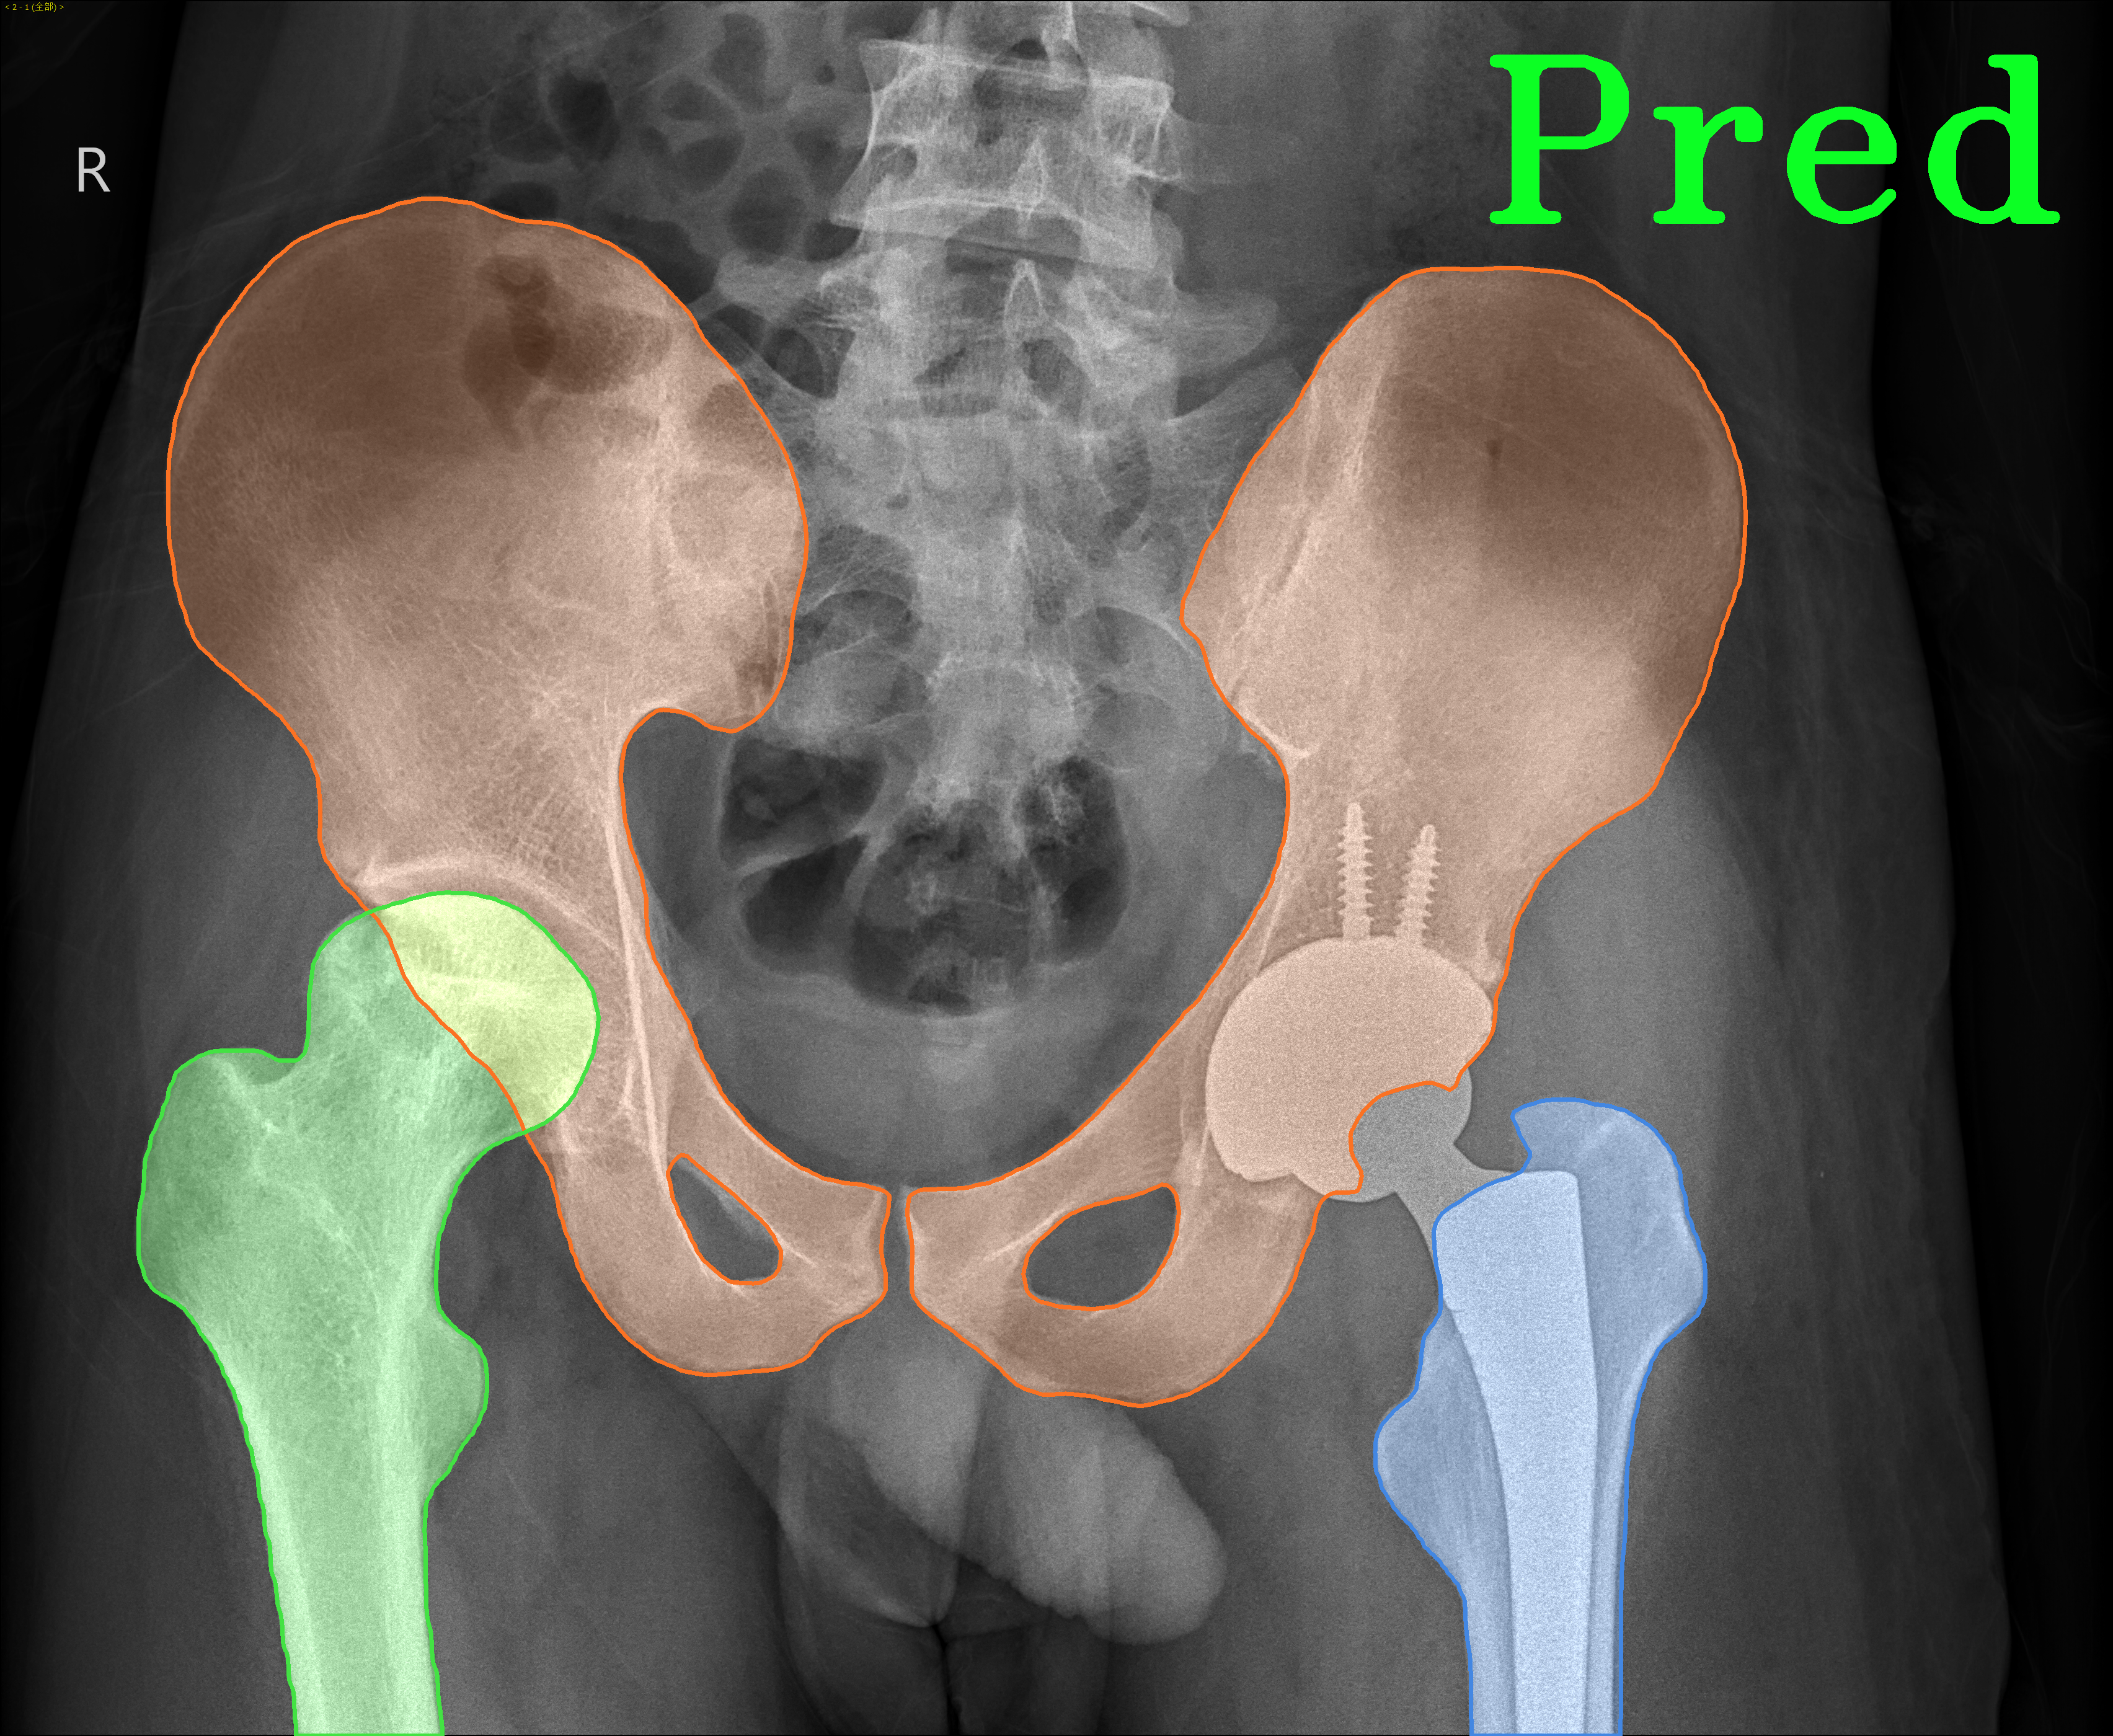

TransFuse is evaluated on both 2D and 3D datasets to demonstrate the effectiveness. As different medical image segmentation tasks serve different diagnosis or operative purposes, we follow the commonly used evaluation metrics for each of the segmentation tasks to quantitatively analyze the results. Selected visualization results of TransFuse-S are shown in Fig. 2.

Results of Hip Segmentation. Tab. 3 shows our results on hip segmentation task, which involves three human body parts: Pelvis, Left Femur (L-Femur) and Right Femur (R-Femur). Since the contour is more important in dianosis and THA preoperative planning, we use Hausdorff Distance (HD) and Average Surface Distance (ASD) to evaluate the prediction quality. Compared to the two advanced segmentation methods [33, 28], TransFuse-S performs the best on both metrics and reduces HD significantly (30% compared to HRNetV2 as well as 34% compared to Unet++ on average), indicating that our proposed method is able to capture finer structure and generates more precise contour.

| Hip Segmentation | |||

|

|

|

|